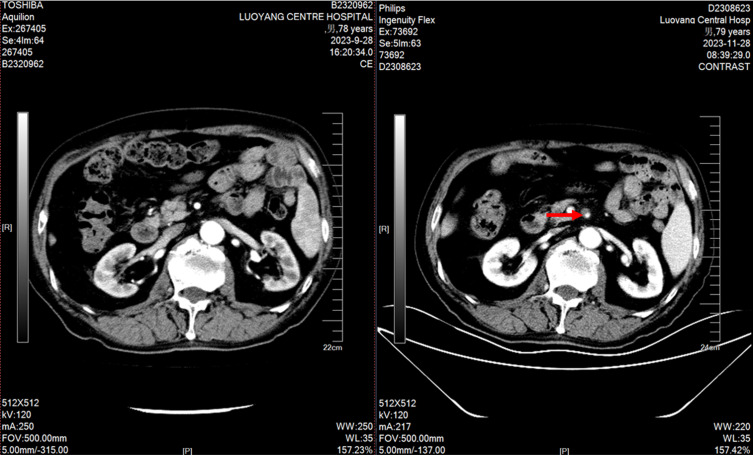

Background: Apatinib mesylate, a VEGFR2 tyrosine kinase inhibitor, is approved for advanced liver, esophageal, gastric and other malignant tumors, but its adverse effects require attention. We report a 79-year-old male with prostatic adenocarcinoma who developed superior mesenteric artery dissecting aneurysm after combined apatinib and chemotherapy. Apatinib, an anti-angiogenic agent, synergizes with chemotherapy. After informed consent, the combination regimen was initiated. Two cycles later, the patient had tolerable intermittent abdominal pain, and CT confirmed the aneurysm. Due to progressive tumor and poor physical status, no further treatment was given as the aneurysm did not affect the disease course. This case report aims to provide insights into the safe application of apatinib in clinical practice.

Case report: In this case report, a 79-year-old male with a height of 172 cms and a weight of 67 kgs who had been diagnosed with prostate adenocarcinoma for over three years. MRI scan indicated that bone metastases increased and enlarged compared with prior test. No significant abnormalities were observed in both physical and blood examinations. The pelvic MRI scan showed a prostatectomy changes, multiple abnormal signals in the bilateral ilium, acetabulum, femur, ischiatic bone, pubis, sacral vertebrae, and part of the lumbar vertebrae.